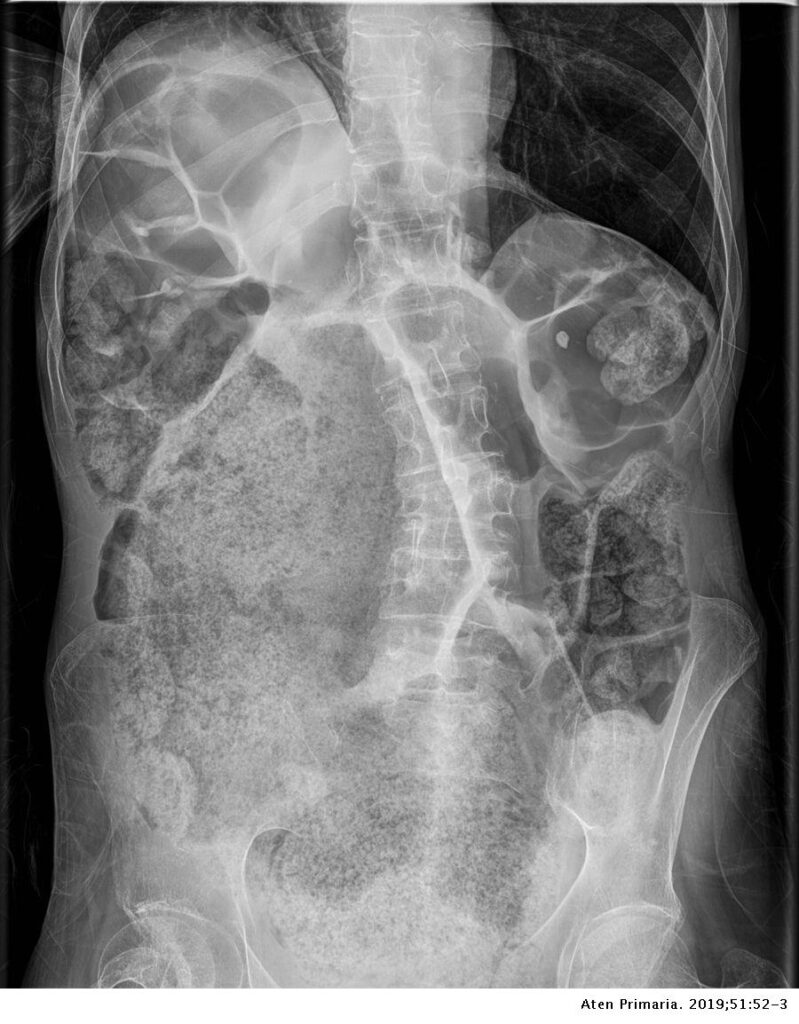

- Obstrucción mecánica: Cuando las heces se acumulan de manera significativa en la bóveda rectal, pueden formar una masa compacta y densa. Esta masa de heces puede crecer gradualmente y ocupar un espacio considerable en el recto y el colon. A medida que esta masa aumenta de tamaño, puede ejercer presión sobre las paredes intestinales y disminuir el espacio disponible para el paso de las heces no retenidas. Esta obstrucción mecánica puede dificultar o incluso impedir que las heces no retenidas avancen normalmente a través del colon.

- Distensión y dilatación: La acumulación prolongada de heces en el colon puede llevar a la distensión y dilatación de las secciones intestinales afectadas. Esta distensión puede agravar la obstrucción, ya que las secciones intestinales dilatadas pueden colapsar sobre sí mismas, estrechando aún más el lumen intestinal y dificultando el paso de las heces.

En conjunto, la retención fecal grave en la bóveda rectal puede ocasionar obstrucción adicional al flujo fecal debido a la compresión mecánica, la alteración de la peristalsis, la dificultad en la evacuación y la distensión del colon. Estos factores combinados pueden llevar a una obstrucción parcial o total del colon, lo que interfiere con la función normal del sistema digestivo y puede generar síntomas como dolor abdominal, distensión abdominal, náuseas y vómitos. La gestión temprana y adecuada de la retención fecal es esencial para prevenir estas complicaciones y garantizar el funcionamiento saludable del tracto gastrointestinal.